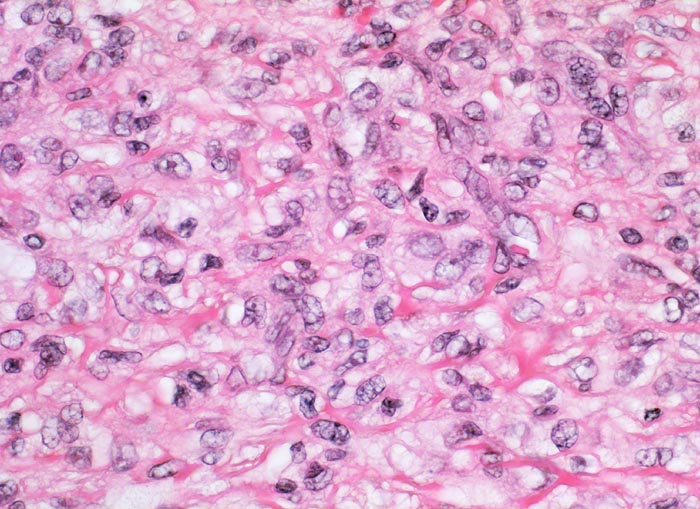

PathoPic – image database / PathoPic ID 4257 - Benignes fibröses Histiozytom

Benignes fibröses Histiozytom

Fibroblastäre Zellen umgeben von einem kollagenfasrigen Stroma. Das reichlich vorhandene Zytoplasma ist vakuolisiert. Die Zellkerne sind rundlich bis länglich mit feinem Chromatin und enthalten einen kleinen eosinophilen Nukleolus.

Auf Schnitt durch das Hautexzisat ist ein gelber unscharf begrenzter intradermaler Knoten erkennbar.

Derber indolenter rotbrauner Knoten am Arm, Durchmesser des Knotens 5mm.

400